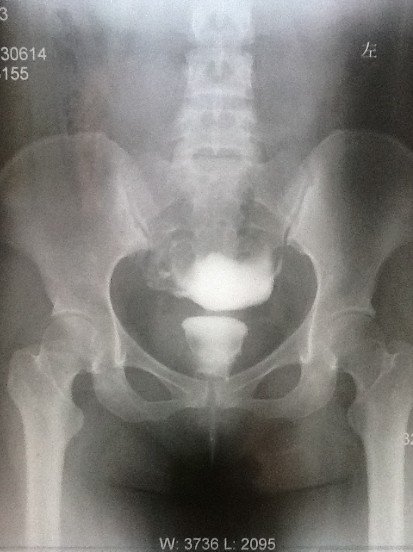

求助:帮我看看输卵管造影片吧

造影剂注入前 造影剂推入十几毫升时  造影剂完全推入  20分钟后的弥散照。 诊断:1.右输卵管炎          2.宫腔粘连         3.盆腔粘连给医生看了后,说我宫腔粘连不明显,有一小缺口可能是气囊,并配了妇炎康复胶囊和妇康消炎栓,治疗炎症。主要还是说盆腔粘连比较严重,需要宫腹腔镜。本人曾有过阑尾炎开刀史和胆囊炎开刀经历,对宫腹腔镜很是畏惧。请专家帮我看看,我的盆腔粘连是不是很严重。不做宫腹腔镜是否还有怀孕机会?